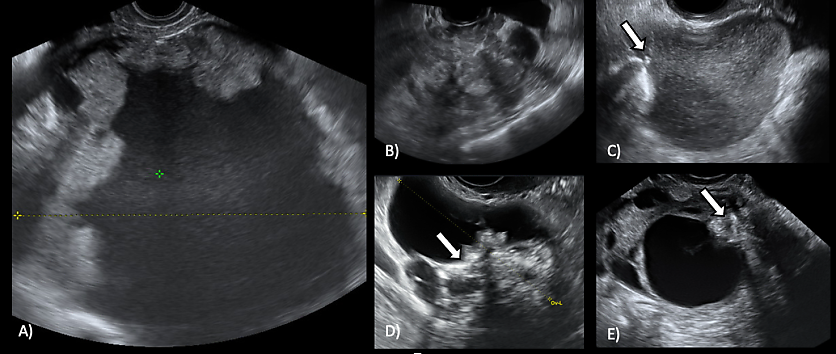

LGSOCs commonly appear as multilocular-solid (55%) or solid (32%) masses (Figure 4). Sonographic features typically include small calcifications in the solid tissue and papillations (32%).10

4

(A–E) Grayscale sonographic images of low-grade serous carcinoma (LGSOC). Arrow indicates echogenic foci consistent with calcifications. As reported by Moro et al., LGSOCs commonly appear as multilocular-solid (55%) or solid (32%) masses.10

In a retrospective analysis of preoperative ultrasound images of malignant serous ovarian tumors, Moro et al. reported an overlap in ultrasound appearance between BOTs and non-invasive LGSOCs, both presenting as cysts with papillary projections.10 Similarly, the authors reported an overlap in ultrasound characteristics between invasive LGSOCs and HGSOCs, as both tumor types appeared as multilocular-solid masses with non-papillary solid components or solid masses. However, HGSOCs were more likely to be solid than were invasive LGSOCs which, in turn, were more often multilocular-solid.10 Moreover, a considerable number of invasive LGSOCs presented hyperechoic foci, which were very rare in the other subclasses of malignant serous ovarian tumors.